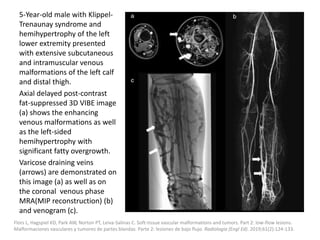

3-month-old boy with

mixed (macro- and

microcystic) lymphatic

malformation containing

blood at different stages

involving left chest wall

and arm.

Axial T2 shows large

extension of lymphatic

malformation, lesion

contains locules of

different sizes and various

signal intensities, some of

which contain fluid-fluid

levels (arrows) indicative of

blood at different stages.

In arm, lymphatic

malformation is causing

mass effect on

musculature (asterisks). L =

lung, H = humerus.

White CL, Olivieri B, Restrepo R, McKeon B, Karakas SP, Lee EY. Low-Flow Vascular Malformation Pitfalls: From Clinical Examination to